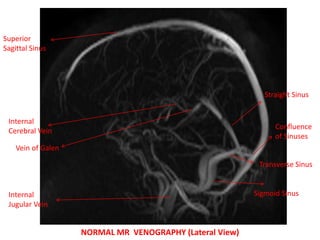

MR VENOGRAPHY

NORMAL MR VENOGRAPHY (Lateral View)

Superior

Sagittal Sinus

Internal

Jugular Vein

Sigmoid Sinus

Transverse Sinus

Confluence

of Sinuses

Straight Sinus

Vein of Galen

Cerebral Vein